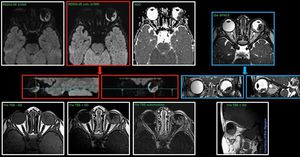

Retinoblastoma with a coil combination of 32ch head and 1 special purpose 4ch @ Siemens 3T Skyra 1 special purpose for the orbit 32ch head coil for the head Not shown all images here from the current case. In front of you only RESOLVE was scanned with 32ch, and the rest of the images 1 special purpose coil.#Siemens_MRI #siemens #mri #retinoblastoma #dwi